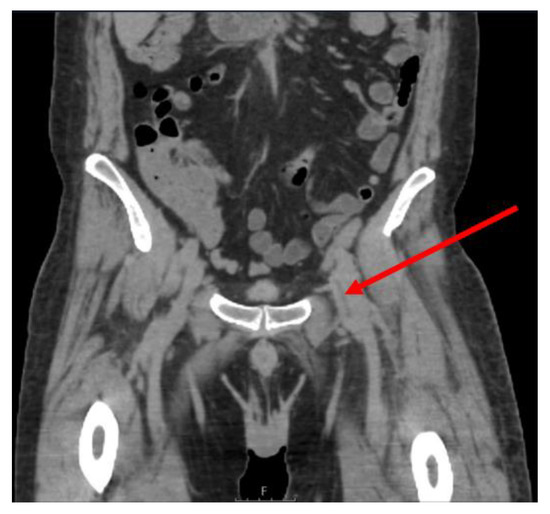

2. Case Presentation